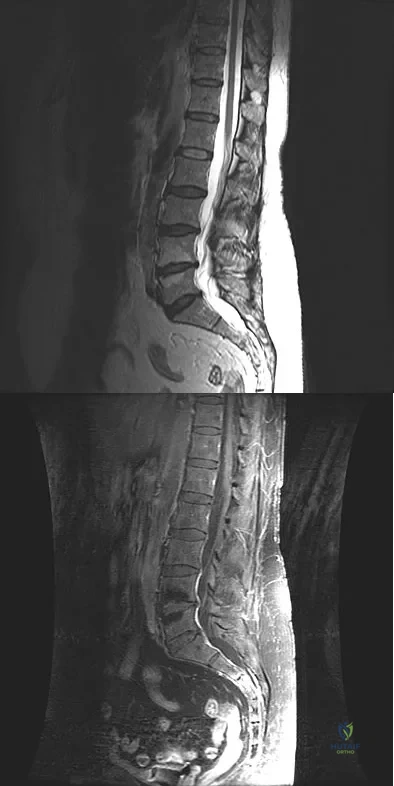

A 42-year-old woman underwent an instrumented posterior spinal fusion at L3-S1 with transforaminal lumbar interbody fusion. She had an excellent clinical result with complete resolution of leg pain. Three months later she now reports increasing back pain and weakness in her legs. Examination reveals weakness in the quadriceps and tibialis anterior. Radiographs show no interval changes in the position of the hardware. MRI scans are shown in Figures 2a through 2c. What is the next most appropriate step in management?

Explanation